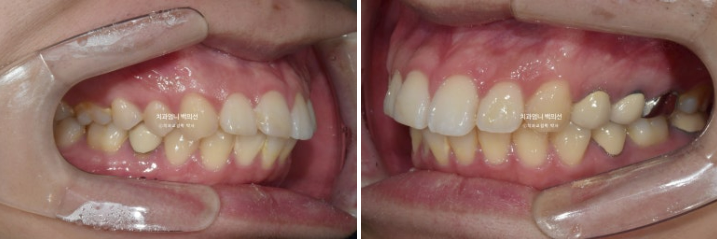

24년 3월까지, 1년 3개월간 70개의 장치를 일주일 간격으로 모두 낀 후 모습입니다.

24.03

중심선은 많이 개선되었으나 여전히 약간의 불일치가 남아있습니다.

1차 세트를 마쳤을 뿐인데도 교합이 좋은편입니다.

앞니 사이 벌어진 틈이 있습니다.

발치공간 1mm가량 남았네요.

이 부분들을 더 개선하고자 재제작에 들어갔습니다.

2022.12~2025.05

발치공간은 깔끔하게 마무리 되었습니다.

중심선과 캔팅의 개선

앞니 돌출의 개선과 적절한 앞니 각도

두번째 재제작으로 교합평면이 수평을 되찾았습니다.